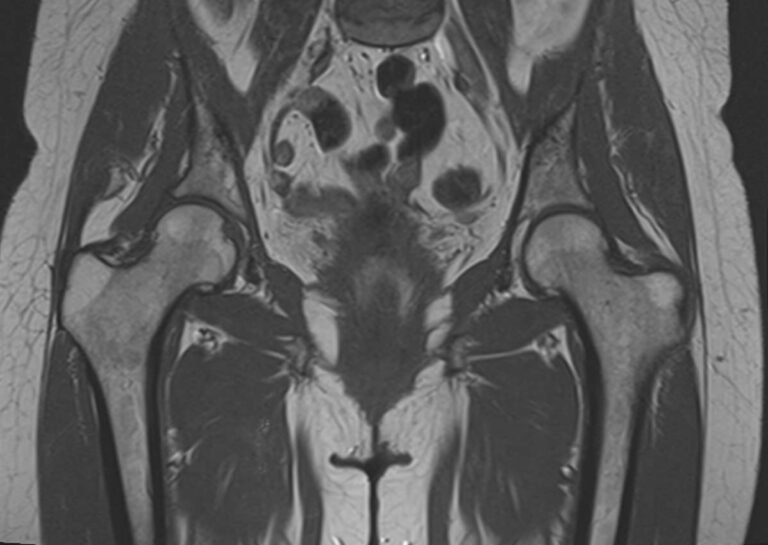

Максимально информативным способом диагностики заболеваний тазобедренных суставов является магнитно-резонансная томография. Кроме высокой информативности МРТ обладает такими преимуществами как достаточная быстрота, безболезненность, неинвазивность и безопасность. Метод основан на использовании действия на ткани внешнего магнитного поля, при этом не применяется вредное рентгеновское излучение. Поэтому МРТ можно проводить столько, сколько необходимо. Например, это бывает важно во время предоперационной подготовки и для динамического наблюдения в ходе лечения, в том числе, в послеоперационном периоде.

В клинике «Доступная медицина» МРТ тазобедренных суставов проводится на новейшем высокопольном томографе экспертного класса TOSHIBA VANTAGE TITAN 1,5 Тесла. Томограф производит сканирование зоны исследования, делая послойные срезы в разных плоскостях с шагом от 1 мм, затем с помощью цифровых приложений преобразует полученные данные в трехмерные изображения превосходного качества. МР томография дает детальную информацию о состоянии костных структур сустава, сухожилий, связочного аппарата, синовиальной оболочки, суставной полости, нервов, сосудов и прилегающих мягких тканей. Это позволяет поставить точный и достоверный диагноз и назначить вовремя лечение.